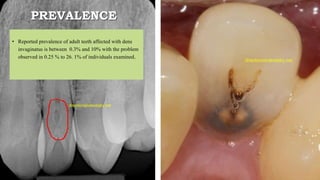

PREVALENCE

• Reported prevalence of adult teeth affected with dens

invaginatus is between 0.3% and 10% with the problem

observed in 0.25 % to 26. 1% of individuals examined.